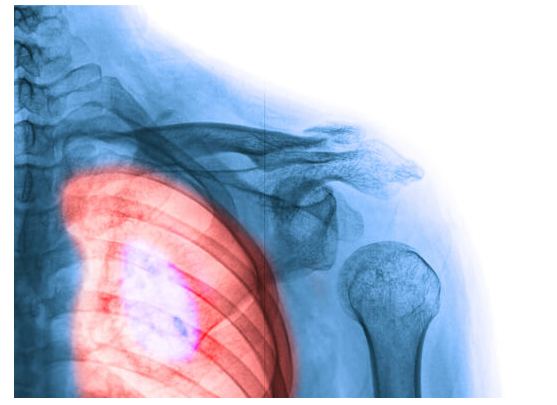

Đây là loại ung thư thường gặp nhất ở phụ nữ, cũng là loại ung thư có tỷ lệ sống cao nhất. Tự khám vú và chụp X-quang tuyến vú là những cách đơn giản giúp phát hiện bệnh sớm. Dưới đây là một số dấu hiệu và triệu chứng của ung thư vú cần lưu ý:

- Xuất hiện u cục bất thường trên vú;

- Đau vú khi có lực tác động vào

- Thay đổi kích thước vú;

- Da vùng vú bị thay đổi màu sắc bất thường;

- Núm vú thụt vào trong.